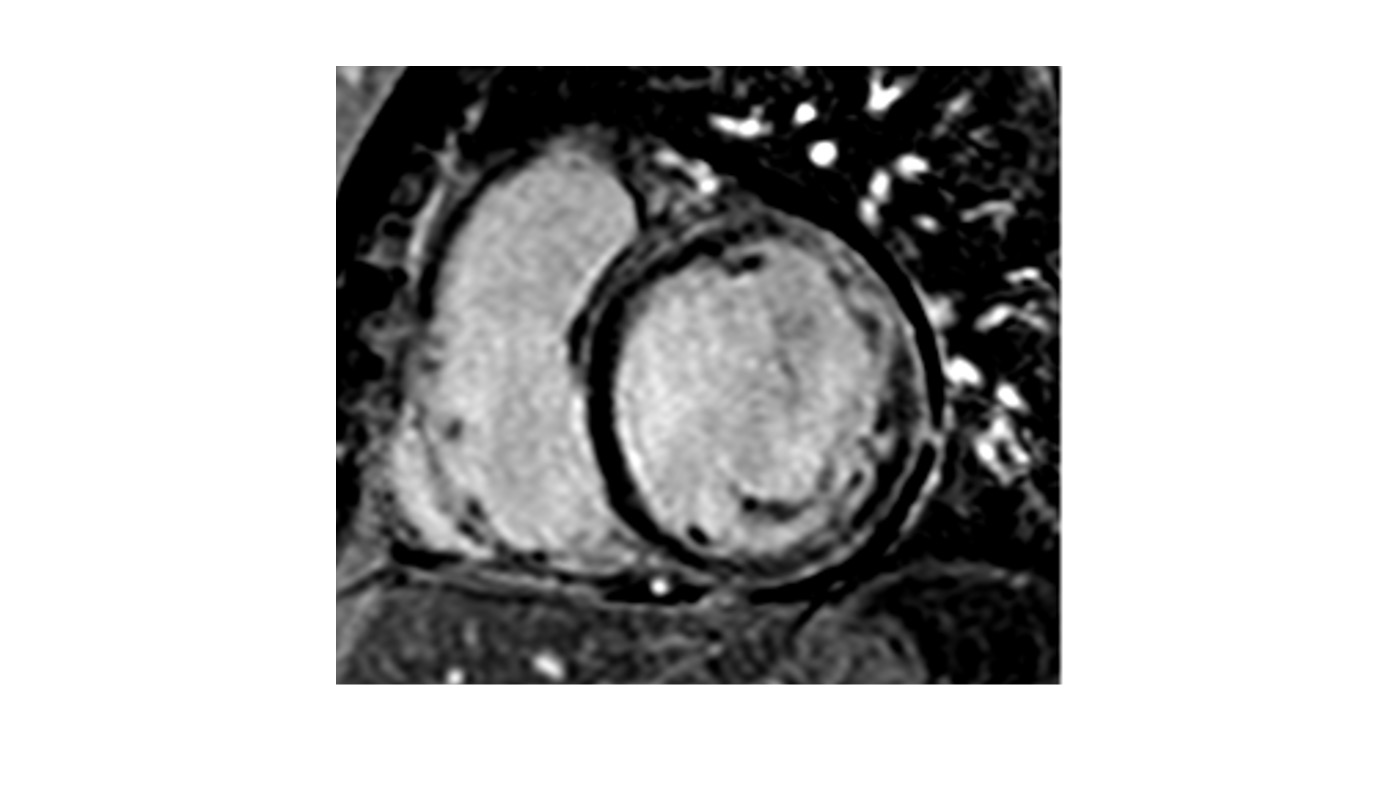

A ring-like LGE pattern on PSIR short-axis view, which is characteristic of genetic cardiomyopathies.